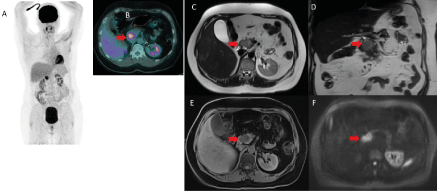

One year later, 3-month imaging follow up by MRI evidenced a 3.5 cm mass of the head of pancreas, hyper-intense on T1, T2 and diffusion weighted images (Figure 2). The patient was asymptomatic and laboratory tests were normal. A new 18F-FDG PET/CT confirmed the presence of a solitary hypermetabolic mass of the head of the pancreas (SUVmax 11.4), in the same localization as compared to the previous 18F-FDG PET/CT, highly suspicious of an isolated pancreatic relapse (Figure 3).

Figure 3. 18F-FDG PET/CT (A-B) and MRI (C-D-E-F) for the diagnosis of the isolated pancreatic relapse. Solitary pancreatic mass associated with a high hypermetabolism on !8F-FDG PET/CT (SUVmax 11.4) and on MRI 3.5cm mass at the head of the pancreas with a hypersignal on axial (C) and coronal(D) T2-weighted MRI without compression on biliary or wirsung duct. This mass appeared as hypo-intense on unenhenced T1-weighted MRI (E) with significant restriction of diffusion at b800 (F). (red arrow)